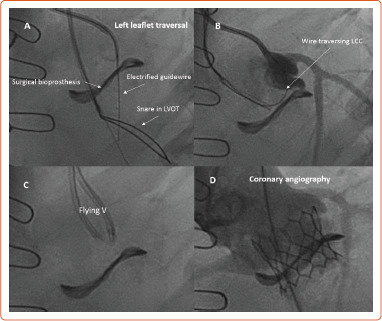

While redo surgical aortic valve replacement has traditionally been the gold standard for the treatment of failed surgical valves, valve-in-valve (ViV) transcatheter aortic valve replacement (TAVR) has arisen as a viable, less invasive option with the potential for improved short-term morbidity and mortality. Retrospective registry data regarding ViV TAVR outcomes have been encouraging, with excellent 1-year mortality, and sustained valve performance and quality of life improvement out to 3 years. Operators must be comfortable with CT analysis for procedural planning, and be able to identify and troubleshoot patients who are at risk for coronary obstruction and patient prosthesis mismatch. The authors provide a review of clinical outcomes associated with ViV TAVR, procedural planning recommendations, and strategies to overcome technical challenges that can occur during ViV TAVR.